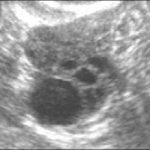

Поликистоз (УЗ-признаки)

УЗИ позволяет обнаружить поликистоз яичников. Яичники увеличены в размерах, содержат множественные кисты, нет ДФ, капсула яичников уплотнена (гипертекоз). Однако, не всем женщинам с кистами яичников ставят диагноз «поликистоз яичников» и наоборот — при ПЯ кисты могут выглядеть нормальными. Поэтому ПЯ диагностируют не только на основе результатов УЗИ, но и при наличии других симптомов — нарушения менструального цикла и гормонального дисбаланса.